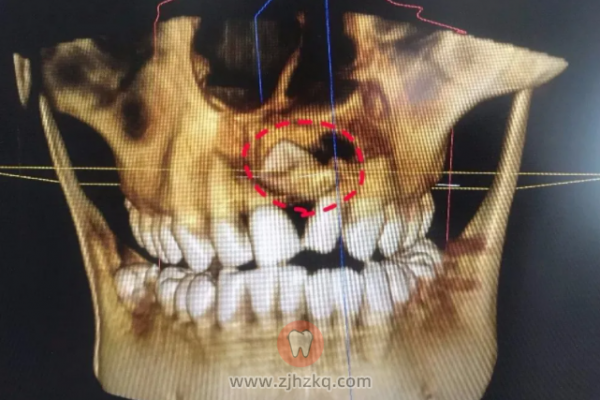

一般可以萌出到口腔的多生牙,肉眼就能看到,而埋伏在颌骨内不萌出的多生牙需采用X光片检查才能发现,因此定期对宝宝牙齿进行检查有着相当大的作用,针对多生牙如能早发现及时拔除,将会减少对恒牙列的影响。

若多生牙是埋伏在颌骨内,患儿年龄较小,牙齿处于形成阶段,手术拔除可能会伤及恒牙胚时可暂缓拔出,应进行观察,重新评估拔牙的时机。拔除时为确定多生牙的数目和位置可借助X线片、曲面断层片或CT,对于埋伏的多生牙如果不产生任何病理变化,对正常牙齿萌出没有阻碍,也可以不处理。